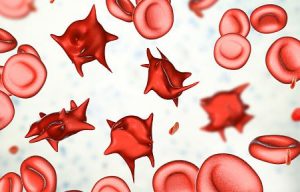

Beim gesunden Blut (links) sind die Blutzellen wie

Billardkugeln und der Sauerstofftransport ist 100%,

Blutzellen der GENgeimpften sind zerknittert,

verhaken sich, provozieren Blutgerinnsel+Thrombosen.

UND: Sauerstofftransport ist kaum noch möglich,

Dauermüdigkeit, weil alle Organe unterversorgt sind.

With healthy blood (left) the blood cells are like

billard balls and there is full 100% oxygen

transport, so the person is sportive and fit. The

blood cells of GENE vaccinated are crumpled, they

stick together forming clots and thromboses. AND:

oxygen transport is hardly possibble, eternal

tiredness comes up because all organs suffer lack of

oxygen.

roten Blutkörperchen so verändern, dass sie

zusammenkleben. Das erklärt die

Arztes, die die Moderna Covid-Impfung(en) erhalten

haben, Blutzellen, die zerstört sind,

mutiert-röhrenförmig aussehen und zusammenklumpen

Effekt? Der Moderna-mRNA-Covid-Impfstoff verändert die

Form und Klebrigkeit der roten Blutkörperchen, wodurch

sie gerinnt. Das erste Diagramm unten zeigt gesunde

Blutkörperchen und nach der Covid-Impfung haben Sie

mutierte, deformierte rote Blutkörperchen,

aufgestockte Proteine und den Klebrigkeitsfaktor, der

tödliche Blockaden verursacht. Es ist wie eine

Also ich kann dazu noch folgendes sagen: Das Blutbild

praktisch aller Geimpften weist ein Verklumpen der roten

Blutkörperchen aus. Damit sinkt die Oberfläche dieser! Die

Folge ist nur logisch = verminderte Sauerstoff Versorgung